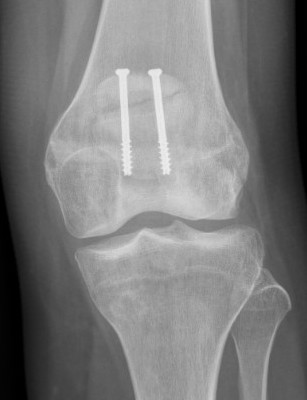

2. Perform TTT (if TTTG > 20)

- incision over TTT

- medialise at least 1 cm

- ensure some element of Fulkerson / anteriorise

- can distalise if patella alta

- secure with screws (2 x small fragment usually sufficient)

- reassess stability